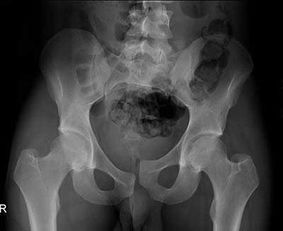

骶尾骨骨折要休息多長時間會好呢,在這期間骨折患者應(yīng)該如何注意自己的飲食呢?那么,請點擊馬上鏈接康復(fù)熱線 骶神經(jīng)損傷嚴(yán)重時可出現(xiàn)跟腱反射消失,但很少出現(xiàn)括約肌功能障礙,予后與神經(jīng)損傷程度有關(guān),輕度損傷予后好,一般一年內(nèi)可望恢復(fù)。